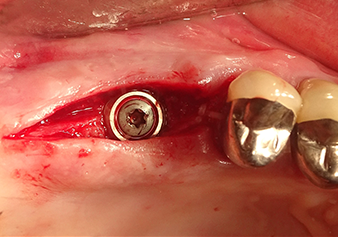

Preoperative findings: The alveolar ridge has healed well, including sufficiently broad, keratinised gingiva

Fig.1: Preoperative findings: The alveolar ridge has healed well, including sufficiently broad, keratinised gingiva.

Following atraumatic preparation of the mucoperiosteal flap, the implant position was marked with the I1 instrument and the site prepared – until initial resistance was felt. Piezosurgical instruments were used in an up and down movement without any pressure being exerted. The piezoelectric vibration produced the desired and efficient cavitation.

The I2A instrument (diameter 2.0 mm) was then used to perforate the sinus floor intermittently and on the smallest scale possible. This special piezosurgical method ensures that the Schneiderian membrane is not damaged. When the Z25P was used, the membrane was already lifted slightly by the coolant supplied via the instrument tip (Fig. 3). The coolant quantity was just 50% in order to avoid high pressure in the implant bed.